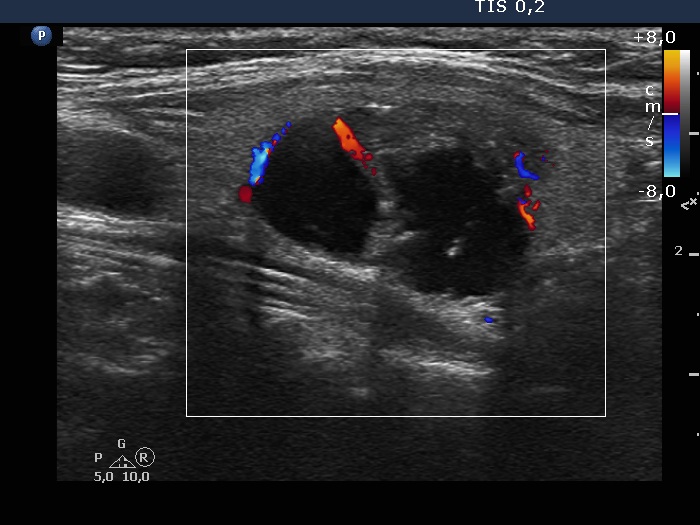

Study on 100 consecutive patients with thyroid nodule - case 042

Three years after the initial examination (ultrasonographic picture 8)

Left lobe, longitudinal view, color Doppler mode. The nodule has both perinodular and intranodular blood flows.